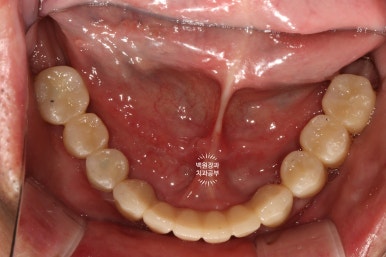

아래턱 임플란트 수술을 하였습니다.

아래턱 치아 12개를 만들어드리는데, 6개의 임플란트만 있으면 됩니다.

약 2주 정도 지나서 아래턱 임플란트 6개를 심어드렸습니다.

위턱의 경우 아까 언급하였듯, 임플란트가 심어질 잇몸뼈가 아래턱에 비해 무르기에 보다 많은 임플란트를 필요로 하지만, 아래턱의 경우 전체 임플란트를 위한 최소한의 임플란트 개수는 6개입니다.

송곳니 2개, 작은어금니 2개, 큰어금니 2개 총 6개의 임플란트만 있으면, 아래 완전틀니를 안쓰시게 될 수 있죠.

확인하실 수 있듯, 아래턱의 경우 단 6개의 임플란트만 심었음에도 불구하고, 총 12개의 치아를 만들어드릴 수 있었습니다. 위턱의 경우 좌측 3개, 우측 1개의 임플란트로 총 5개의 치아를 만들어드린 상태입니다.

이렇게까지 제작해드리는데, 위턱에는 4개의 임플란트 아래턱에는 6개의 임플란트만 사용하였을 뿐입니다.

다행이라면 60대 남성분임에도 불구하고, 악궁이 작으신 편이라 12개의 치아만으로도 충분히 불편하지 않게 식사가 가능하셨습니다.